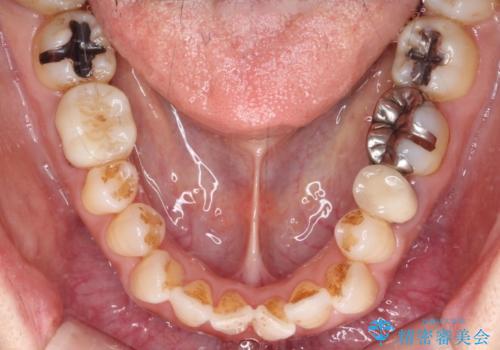

銀歯を白くしたい セラミックによる審美歯科治療

- 奥歯の銀歯をセラミックの白い歯にして、しみる症状も改善したいとのことで来院された患者様です。

知覚過敏の症状が強い歯と、銀歯の範囲や銀歯の下のむし歯が大きい歯は、インレー修復では対応が難しいためオールセラミッククラウンで、インレー修復で対応が可能な歯ではセラミックインレーにて修復することとしました。